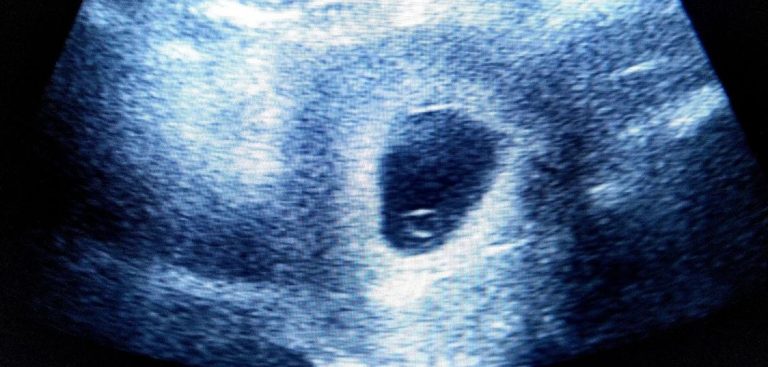

متى يبدأ نبض الجنين متى يبان نبض الجنين بالسونار؟ وأعراض ظهور نبض الجنين أبريل 9, 2022 · Mirna Shewil متى يبان نبض الجنين؟ اقرأ المزيد ←